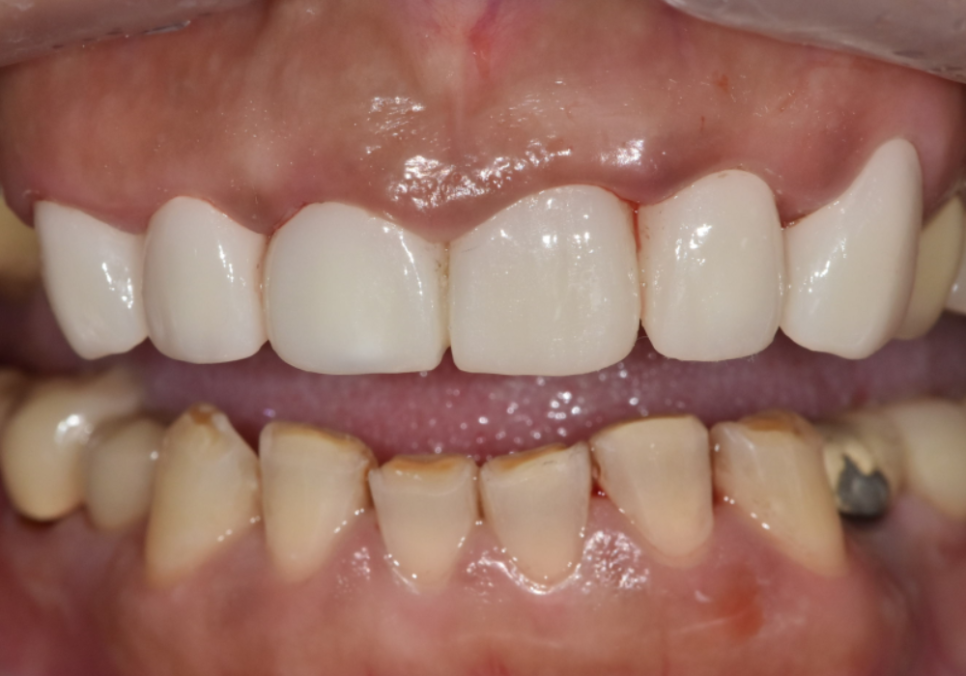

251223

입안을 살펴보니...

브릿지 경계 라인이 조금 까맣게 비쳐보이고

잇몸도 꽤 부어있는 걸 확인할 수 있었습니다.

환자분께서는 이번 기회에

앞니의 모양과 색상을

더 가지런하게 바꾸길 원하셔서

총 6개의 치아(#13~23)를 연결하는

지르코니아 브릿지를 제작해 드렸습니다.

251223(전) 260312(후)